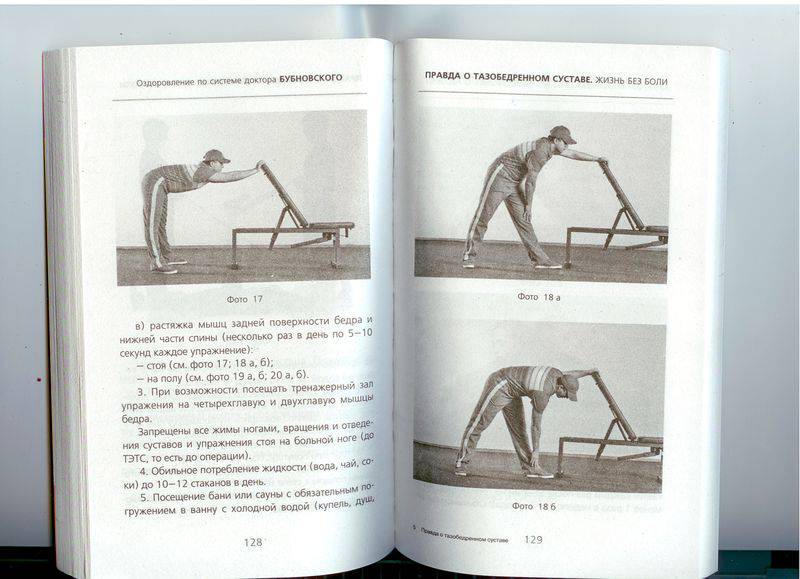

Гимнастика Кегеля для мужчин: упражнения для простаты

Раздел: Идеи и советы